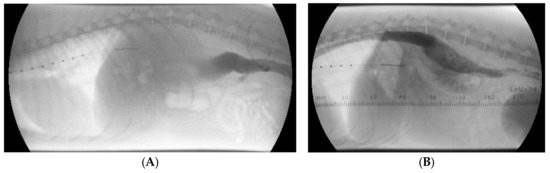

At presentation, the dog was bright, alert, and responsive with a body condition score of 4/9. The respiratory rate was 56 breaths/minute without effort. The femoral pulse quality was fair, and it was symmetrical with a rate of 144 beats/minute. Rectal temperature was 38.9 degrees Celsius. The buccal mucous membranes were pink, with a capillary refill time of 1 s. Cardiac auscultation revealed no murmur or arrhythmia. During a short walk within the clinic from the reception area to the cardiology room, the dog collapsed. During this episode, the femoral pulses could not be felt. Surface electrocardiogram was performed immediately, which showed sinus tachycardia with a rate of 200 beats/minute. Echocardiography showed a severe left ventricular underfilling with severe concentric (pseudo) hypertrophy (Figure 1), and a low peak aortic flow velocity measured from the subcostal view (Table 1). Blood tests were performed. Serum troponine-I concentration was within the reference range (0.01 ng/mL; reference interval [RI], <0.06 ng/mL) making a primary left ventricular hypertrophy unlikely. Basal cortisol concentration (323 nmol/L; RI, >55 nmol/L) was high enough to rule out hypocortisolism. The antigen test for Angiostrongylus vasorum infection was negative. N-terminal pro Brain Natriuretic Peptide (NT-proBNP) concentration was moderately elevated to 971 pmol/L. A 24 h Holter ECG was performed, which revealed sinus tachycardia during the two syncopal episodes that occurred during the registration. The heart rate during the registration varied between 32 and 265 beats/minute, and it was a sinus rhythm with occasional premature atrial complexes, maximal 3 beats/hour.

Twelve days after the initial visit a second consultation was planned. Blood pressure measurements on multiple extremities were performed to rule out aortic coarctation as a possible cause of the left ventricular concentric hypertrophy. Systolic blood pressure measured on the tail, a front leg, and a hind leg excluded aortic coarctation. Echocardiography was repeated and showed no abnormalities at all. Left ventricular internal and wall dimensions (Figure 1) as well as the peak aortic flow velocity were all within reference ranges (Table 1).

Figure 1. Transthoracic right parasternal two-dimensional grey-scale echocardiographic images at initial presentation (A,C) and 12 days later (B,D). All images show an end diastolic frame. Standard longitudinal four-chamber images (A,B) and standard short-axis images at the level of the papillary muscles (C,D) show at the initial presentation a severe underfilling of the left ventricle with severe concentric pseudohypertrophy, and normal wall- and lumen-dimensions 12 days later.